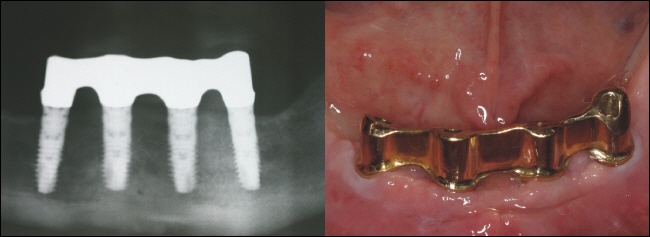

![]() |